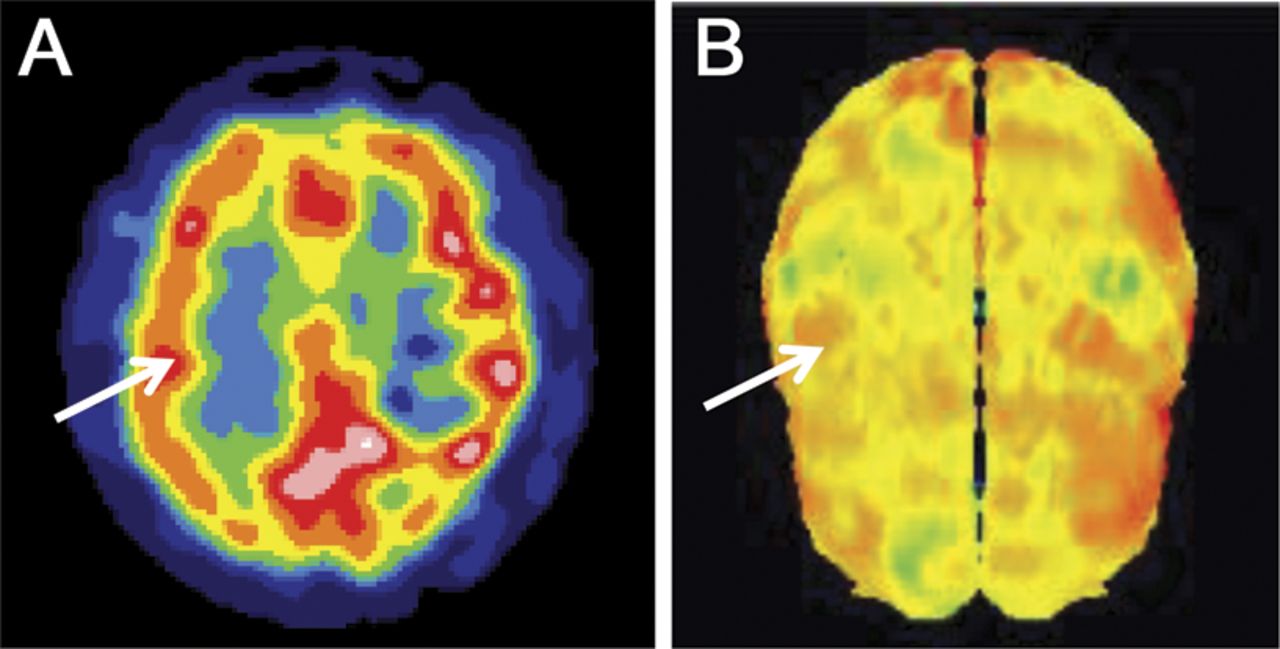

图2

患者的脑SPECT图像

(一)轴向视图的SPECT frontoparietal水平。(B) 3 d皮质灌注SPECT图像在同一水平。箭头表示低灌注的frontoparietal地区。